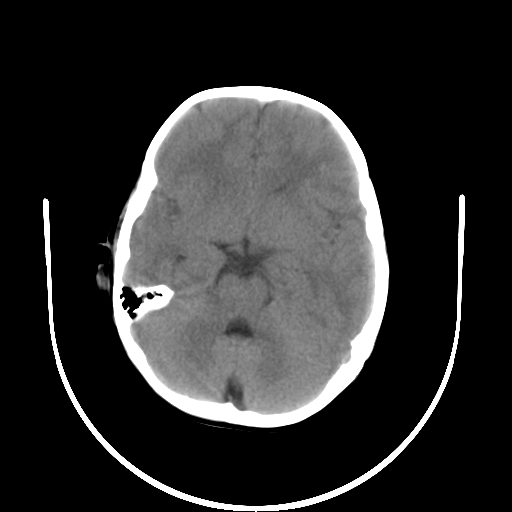

以下是引用深泽交通医院在2009-10-16 8:25:00的发言:[br]右眼环出血伴异物

以下是引用卜一在2009-10-16 15:01:00的发言:[br]右眼球挫裂伤伴异物!

以下是引用拾荒者在2009-10-17 18:38:00的发言:[br]鼻面部皮下积气,右侧睑缘及眼球壁高密度异物影,左侧眼球壁晶状体内侧缘处是圆形低密度影。低密度异物?应提请眼科医生注意。